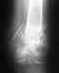

После перелома (вколоченный) пяточной кости без смещения развился артроз в таранно-пяточном суставе (посттравматический артроз). Хожу более менее нормально (хромота еще присутствует). В зависимости от нагрузки если «перехожу» то есть достаточно много стою или хожу в течение дня, то к вечеру появляется боль. Как правило, за ночь боль проходит. Сильного дискомфорта я не испытываю (так как стараюсь контролировать нагрузку), только когда перехожу (из-за работы), и в этот момент желание сделать операцию доминирует. Дистрофии икры нету. Перелом был год назад. Думаю пойти на артродез, более эффективного лечения на сегодня наверно нету. Но боюсь оперативного вмешательства. Есть ли смысл в моей ситуации делать операцию или отложить "до последнего". И полечиться консервативно или это только убирает симптомы и рано или поздно операцию придётся сделать (возможно, чем раньше тем лучше?). И хочется узнать минусы артродеза, чем грозит неподвижность данного сустава. Чего можно плохого ожидать от этого в будущем. И используются при связывании суставов «инородные» предметы (шурупы и т.д.) простите за дилетантский вопрос. Снимок выкладываю последний сделан 03.07.2010 если необходим актуальный снимок, напишите, сделаю, размещу.

• Кликните для загрузки файла 03 07 2010.JPG

270KB (277301 bytes)